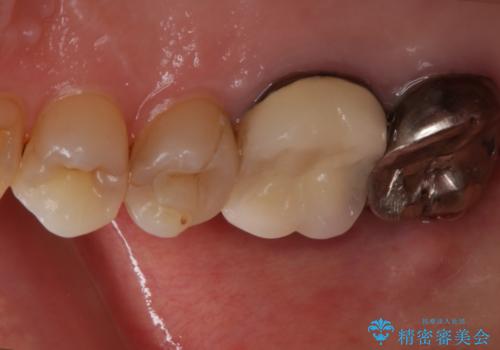

- 元々は別の部位の治療で通われていた患者様でしたが、ニキビのようなものが繰り返しできたり消えたりするとのことで、治療介入を行いました。

根管治療を再度行うことでフィステル(ニキビのようなできもの)は消失しました。最終的にセラミッククラウンによる補綴治療を行いました。

根の病気に対しての治療を行う際、特に再治療の場合においては、無菌的な処置を行うことはもちろん、十分な知識と技術を持つ歯科医師による治療をお勧めしています。

今回の患者様も院長による治療をご希望されたため、福本院長に精密根管治療を行っていただきました。